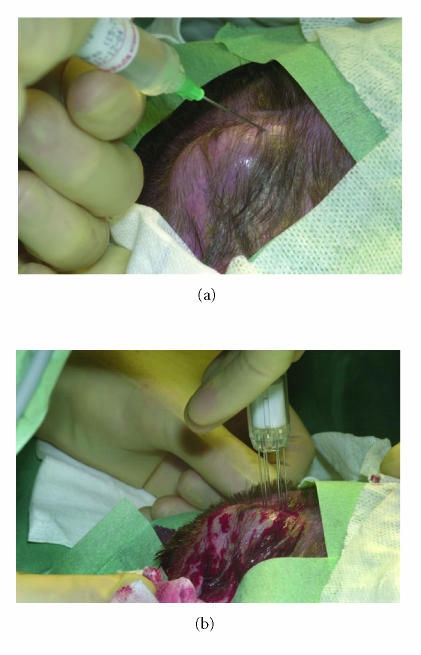

Since no accepted standard treatment was left, we decided to propose an experimental approach in the form of intratumoral injection of bleomycine with electroporation therapy. After informed consent was obtained, the lesion of 50 × 35 mm was uniformly infiltrated with 60 USP-E bleomycin (4 USP-E/mL) under general anesthesia. After five minutes the tumor and a safe margin of 0.5 cm were electroporated using a six-needle array applicator connected to the MedPulser system (Genetronics Inc, San Diego, California), which transforms sinusoidal electrical energy pattern [10]. Tumor and margin were treated with 63 overlapping applicator placements (Figure 6). Gradually the tumor became increasingly necrotic and demarcated from the surrounding tissue. The wound was covered by hemorrhagic crusts. He had no pain complaints. After 10 weeks no tumor was seen anymore. Secondary healing started from the margins of the wound (Figure 7). Two months after EPT he developed a recurrence in his neck, for which he was treated with ifosfamide. This wound healing was delayed due to his chemotherapy courses. He is presently (17 months after electroporation) without disease on his scalp and is doing reasonably well.

Figure 6.

(a) Intralesional injection of bleomycin. (b) Electroporation therapy.